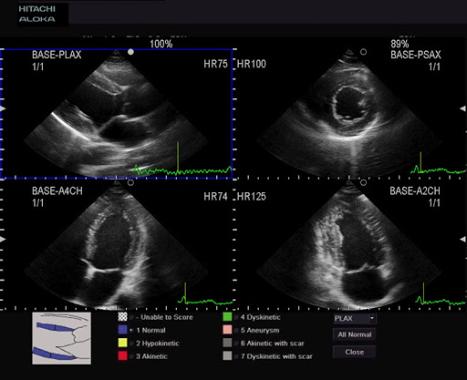

- Широкий кардиопакет

- M-режим, цветной и тканевой М-режим

- Встроенные расчёты и измерения для всех типов исследований, включая кардио и TCD